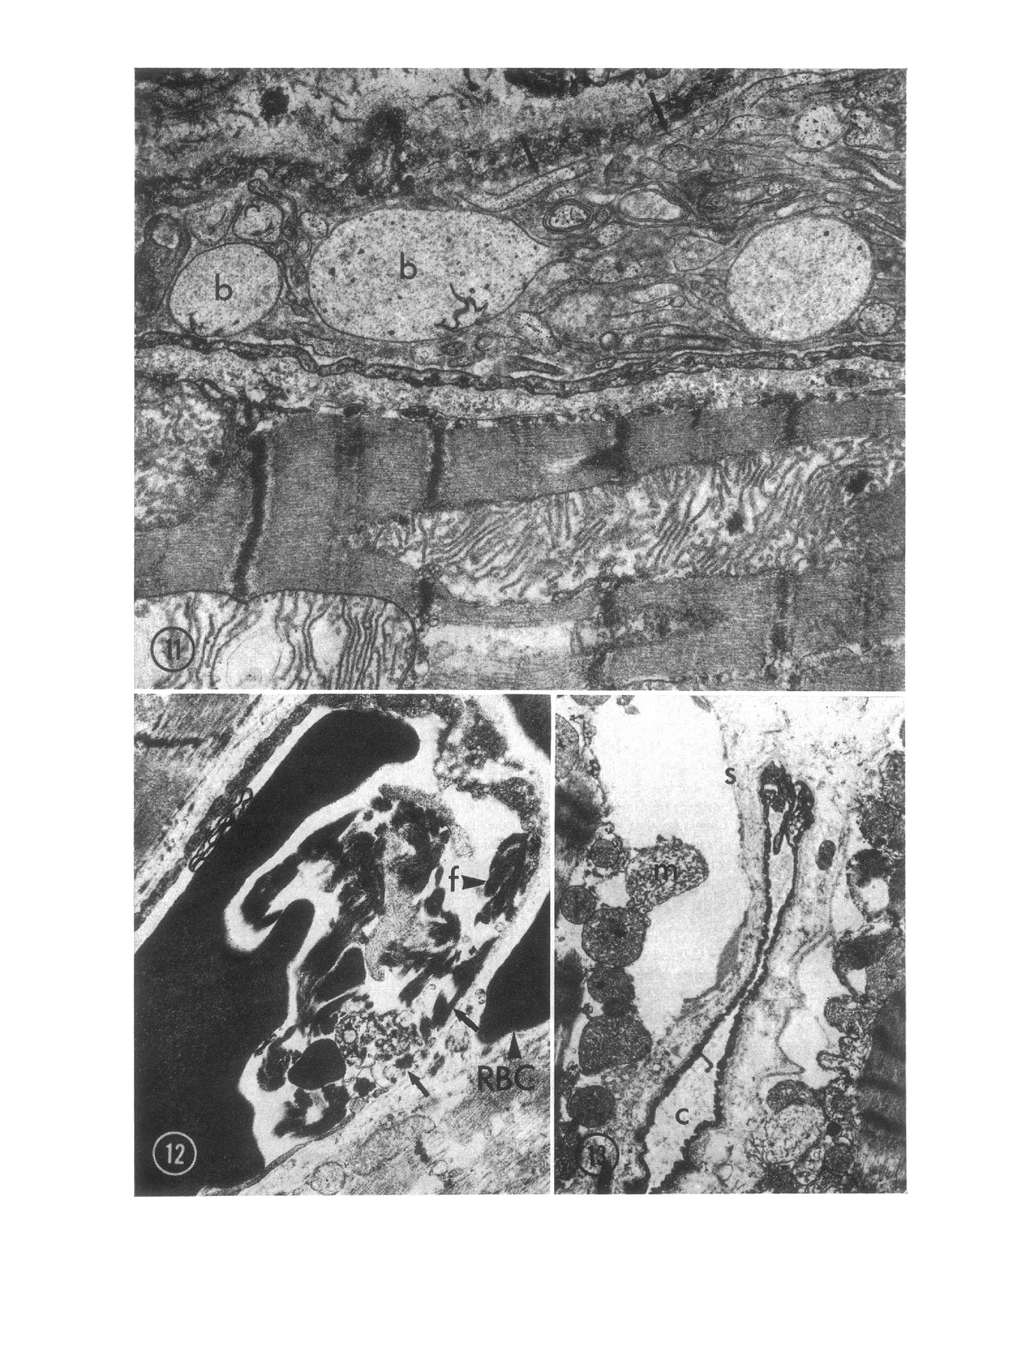

The role of microvascular damage in the genesis of the “no-reflow” phenomenon was investigated in the left ventricular myocardium of dogs subjected to temporary occlusions of a major coronary artery for 40 and 90 min. Intravenous carbon black or thioflavin S (a fluorescent vital stain for endothelium) were used to demonstrate the distribution of coronary arterial flow in control and damaged myocardium. These tracers were injected simultaneously with release of the coronary occlusion or after 5 or 20 min of reflow of coronary arterial blood. After 40 min of ischemia plus arterial reperfusion, usually the tracers were evenly distributed throughout the damaged tissue at each time of reperfusion. On the other hand, when reflow was allowed after 90 min of ischemia, portions of the inner half of damaged myocardium were not penetrated by the tracers. Electron microscopic study of this poorly perfused tissue revealed severe capillary damage; endothelial cells with large intraluminal protrusions and decreased pinocytic vesicles were common. Also, occasional intraluminal fibrin thrombi were noted, as well as extravascular fibrin deposits and erythrocytes. Myocardial cells were swollen in both poorly perfused and well-perfused irreversibly injured tissue. Contraction bands and mitochondrial Ca2+ accumulation were prominent features of irreversible injury with reflow at 40 min but were not noted after 90 min of ischemia in areas with poor perfusion. These results suggest that 40 min of ischemia were tolerated by the capillary bed of the dog heart without serious capillary damage or perfusion defects, but that 90 min of ischemic injury was associated with the “no-reflow” phenomenon, i.e., failure to achieve uniform reperfusion. This failure of reflow was associated with extensive capillary damage and myocardial cell swelling. Death of severely ischemic myocardial cells in this model occurs before the onset of capillary damage and the no-reflow phenomenon.